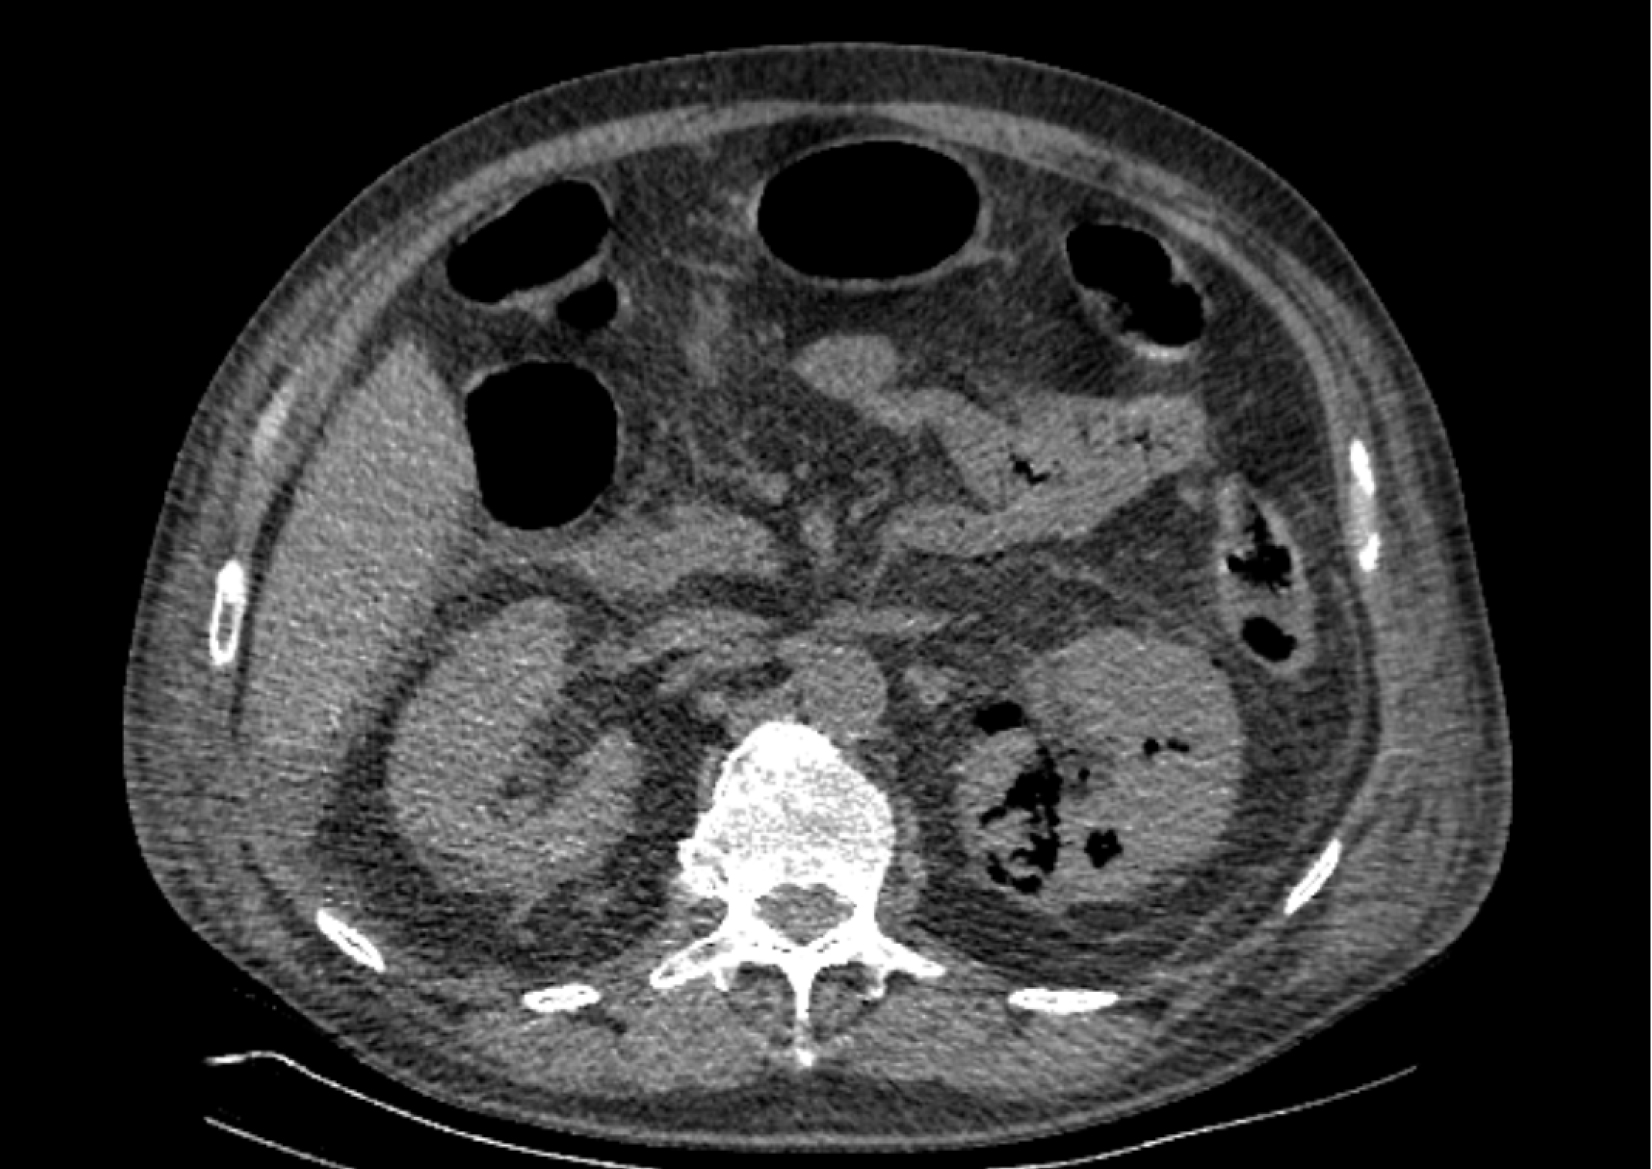

На следующий день состояние пациента оставалось тяжелым, с отрицательной динамикой, креатинин сыворотки возрос до 735,2 ммоль/л, Появились жалобы на слабость, тошноту. При осмотре: живот мягкий, вздут по всем отделам, при пальпации болезненный. Область почек не изменена, при пальпации безболезненна, патологических изменений в области почек не выявлено. Симптом поколачивания отрицательный билатерально. При УЗИ были обнаружены плевральный выпот по 300–400 мл с каждой стороны, гепатомегалия, увеличение размеров селезенки, асцит. Кроме того, в обеих почках были визуализированы тени, характерные для конкрементов. По данным компьютерной томографии (КТ) конкрементов не обнаружено, но в лоханке, на всем протяжении левого мочеточника и, частично, в правом мочеточнике, а также в мочевом пузыре визуализировался газ (рис. 1–6).

Рис. 4. Компьютерная томография органов брюшной полости, забрюшинного пространства, органов малого таза. Газ в почках